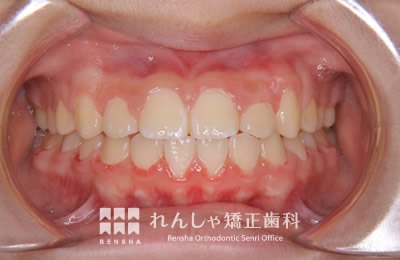

中高生

永久歯列はほぼ完成してしますが、歯列を側方だけでなく後方へも拡大し、埋まっていた右上奥歯を引っ張り出しています。

| 主訴 | 埋まったままでてこない歯がある |

|---|---|

| 診断名 | Angle Class II 小臼歯の埋伏と叢生を伴う上顎前突 |

| 初診時年齢 | 13歳5か月 |

| 装置名 | マルチブラケット装置 |

| 抜歯非抜歯 | 非抜歯 |

| 治療期間 | 2年3か月 |

| 費用の目安 | 約82万円+消費税(検査料金、都度の処置費用等も合わせた総額) |

| リスク副作用 | 歯の移動に伴う軽微な歯根吸収、歯槽骨吸収、歯肉退縮(本症例では軽度の歯根吸収を認めた)、矯正器具装着中のカリエスリスク増大(本症例ではカリエス発生無し) |